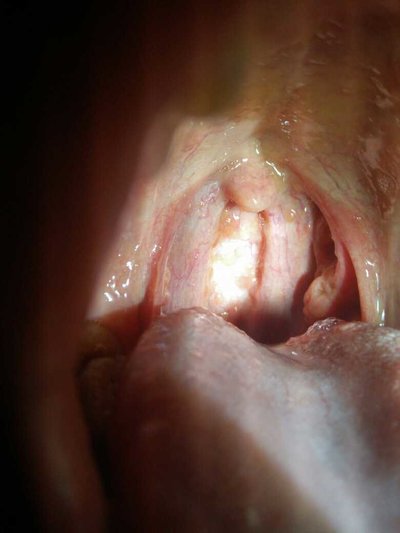

Mainly virus and bacteria infection. Most of them are infected by droplets or direct contact. The pharynx of the human body is the passage behind the nasal cavity and oral cavity, which can be divided into three parts: nasopharynx, oropharynx and laryngopharynx. Pharynx is rich in lymphoid tissue, they gather into a mass called tonsil.

Because the pharynx is rich in lymphoid tissue, the pharynx is one of the main portals for the body to block pathogens, especially the invasion of pathogens. However, due to the complex structure of the pharynx, it is easy to deposit food residues and other foreign bodies, so bacteria are easy to stop, reproduce and cause inflammation in the pharynx.